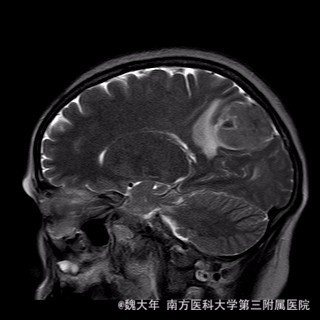

52岁,女性,因“反复头痛10余年,加重1年”入院。患者10余年前无明显诱因始出现头痛,表现为全头发作性胀痛,反复发作,无伴头晕、恶心,无呕吐、肢体抽搐,自行服药(具体不详)及休息后缓解,未予特殊处理。1年前患者觉头痛逐渐加重,以右顶部为甚,劳累或日晒后加重,无头晕、视物旋转,无恶心、呕吐,无发热、寒战,休息或平躺后症状稍有缓解,自行服药不能改善,至当地医院就诊,查颅脑MRI和CT提示“右侧顶部脑膜瘤”。

行“右顶开颅右顶部矢状窦旁脑膜瘤切除术”。取右顶马蹄形手术切口 ,颞侧翻开皮瓣,电刀切开骨膜,中线矢状缝上前、后极各钻一孔,颞侧后方钻一孔,铣刀铣一长方形(7*6cm)骨瓣,见硬膜表面较多点状渗血,予充分止血,悬吊硬膜。 显微镜下切除肿瘤:沿肿瘤边缘剪开硬膜后,见一大小约5*5*6cm肿瘤,沿硬膜内侧面呈匍匐状生长,边界与脑组织有蛛网膜分隔,质地较韧,基底与矢状窦关系密切,靠内侧与大脑镰粘连紧密,血供丰富。仔细分离肿瘤与脑组织的粘连,全切除肿瘤。肿瘤基底与矢窦粘连紧密,并破坏矢状窦侧壁,予低功率电刀反复烧灼,直至肿瘤无明显血供表现。严密止血后常规关颅。